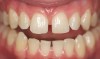

In Case 3, diastemas between front teeth were closed with composite. The maxillary lateral incisors were increased in size to be proportionately correct to the central incisors. Completion required all 12 principles of composite restoration (Figure 6 through Figure 9).

Figure 6  Multiple diastemas requiring closure to improve smile design.

Figure 6

Figure 7  Diastema closure with composite.

Figure 7